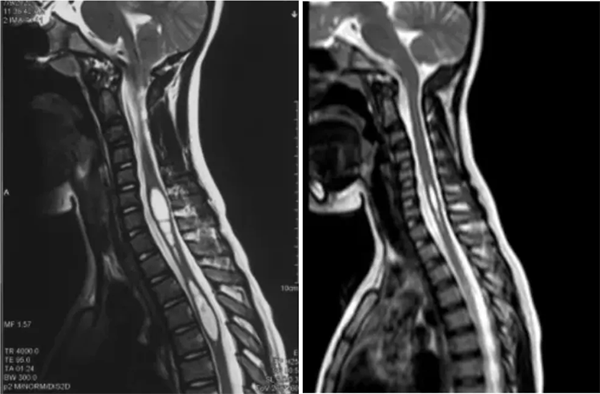

病例2:9岁,四重减压

术前术后对比